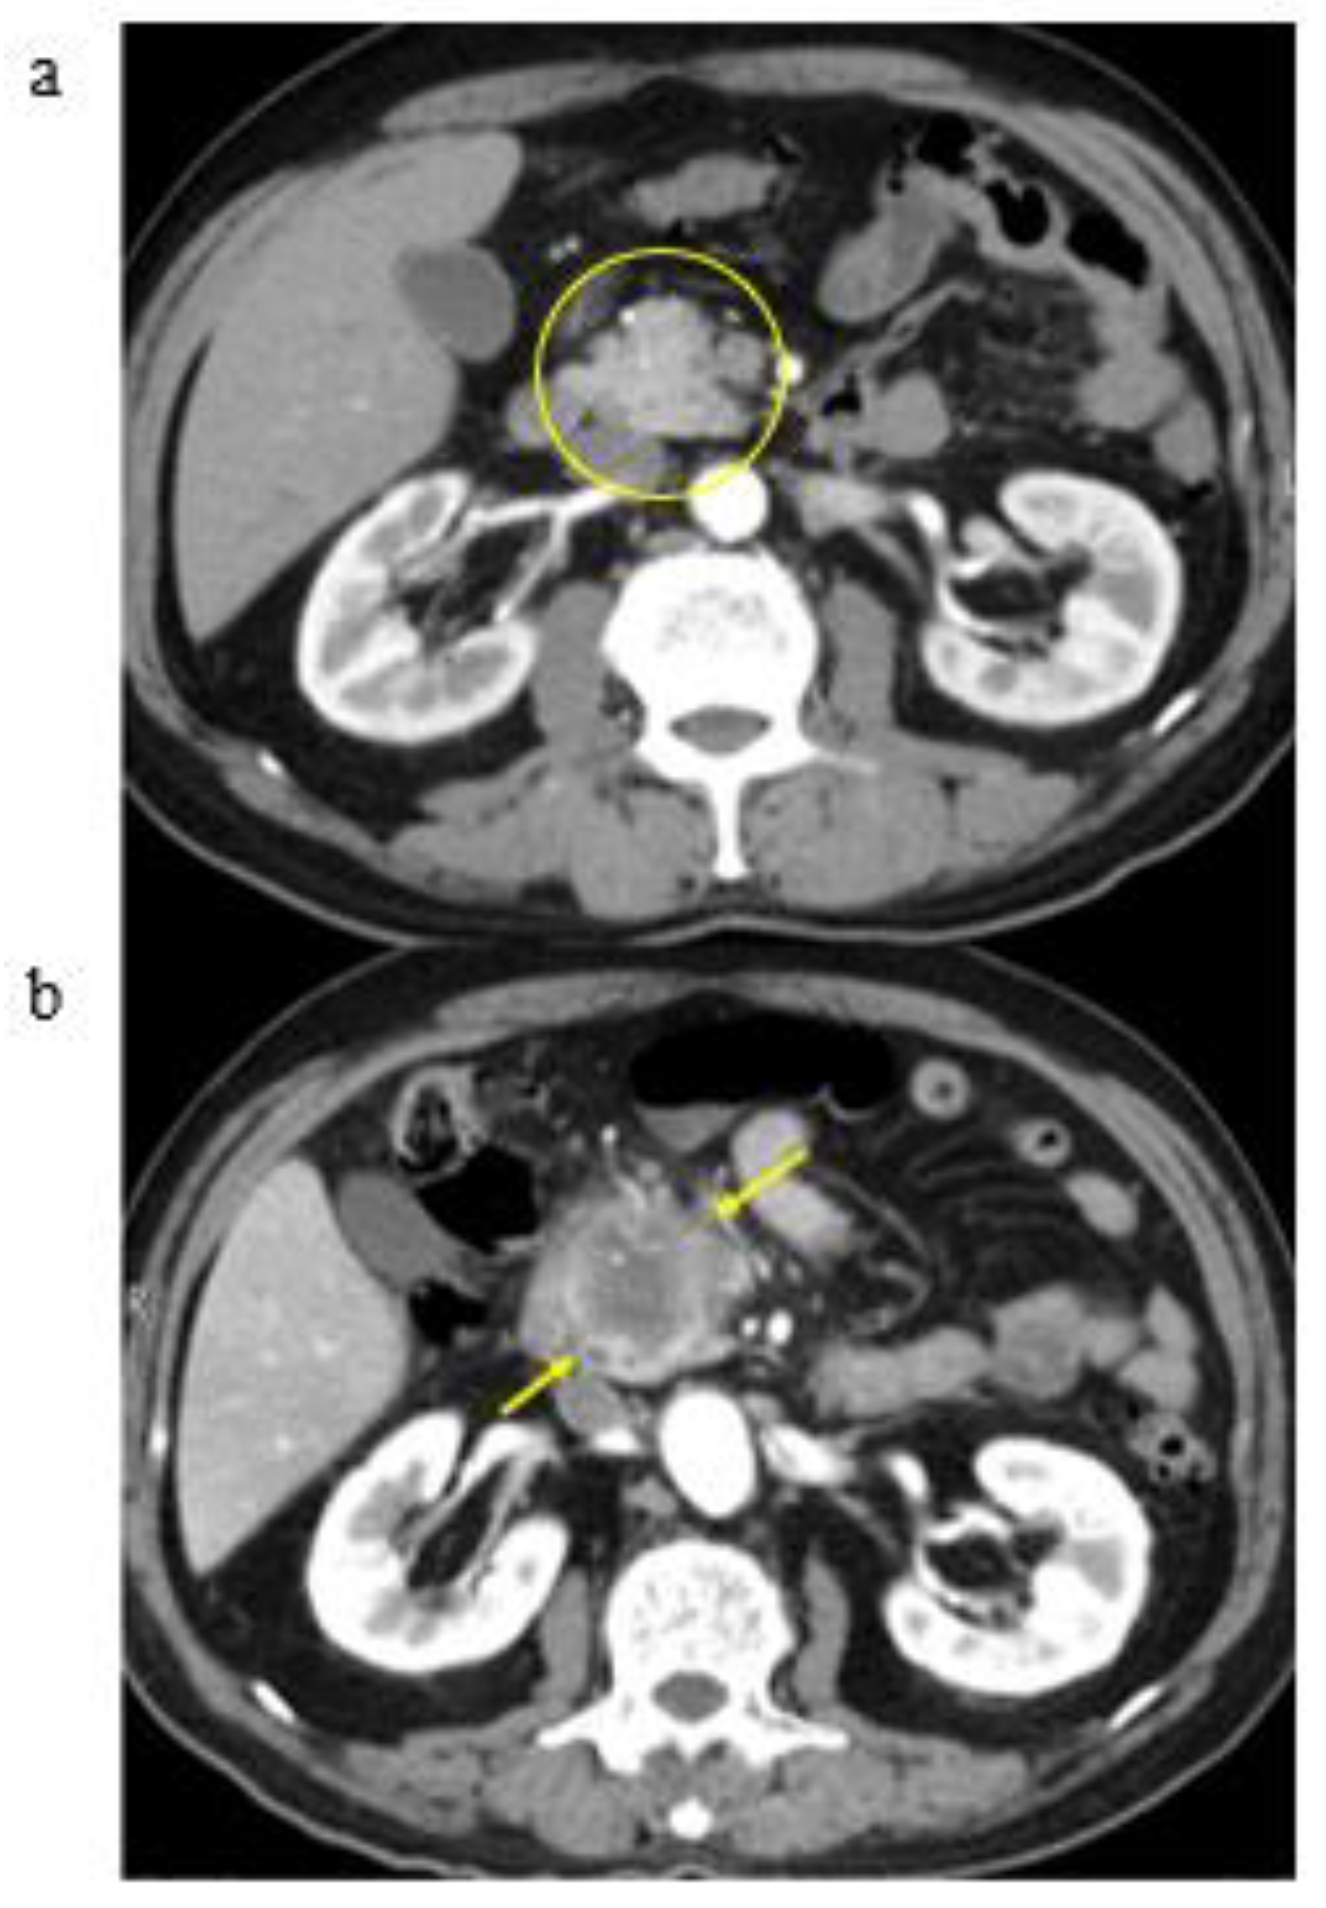

3.2. A Representative Case and Classification by Specific Abnormality of the Pancreas